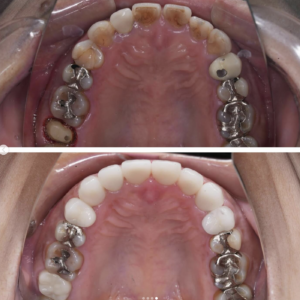

口腔内を全体的に治療させて頂いた患者様の症例です。

もともと透明感の無い大きなセラミックが入っていた前歯に、透明感がありスマートな形のセラミックを入れました。また、歯茎のラインにも違和感があったため、今回の治療で治しています。

セラミックと歯茎の境目が綺麗になるかどうかは歯科医の腕次第ですが、とても綺麗にできたと思います。

また、インプラントなどで奥歯の噛み合わせも治療いたしました。

前歯の審美性にご満足いただき、以前より食事がしやすくなったとお褒めの言葉を頂きました。

当院では噛み合わせなどの機能面や審美性を考えた上での全体的な治療が可能です。